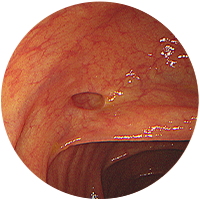

대장게실

-